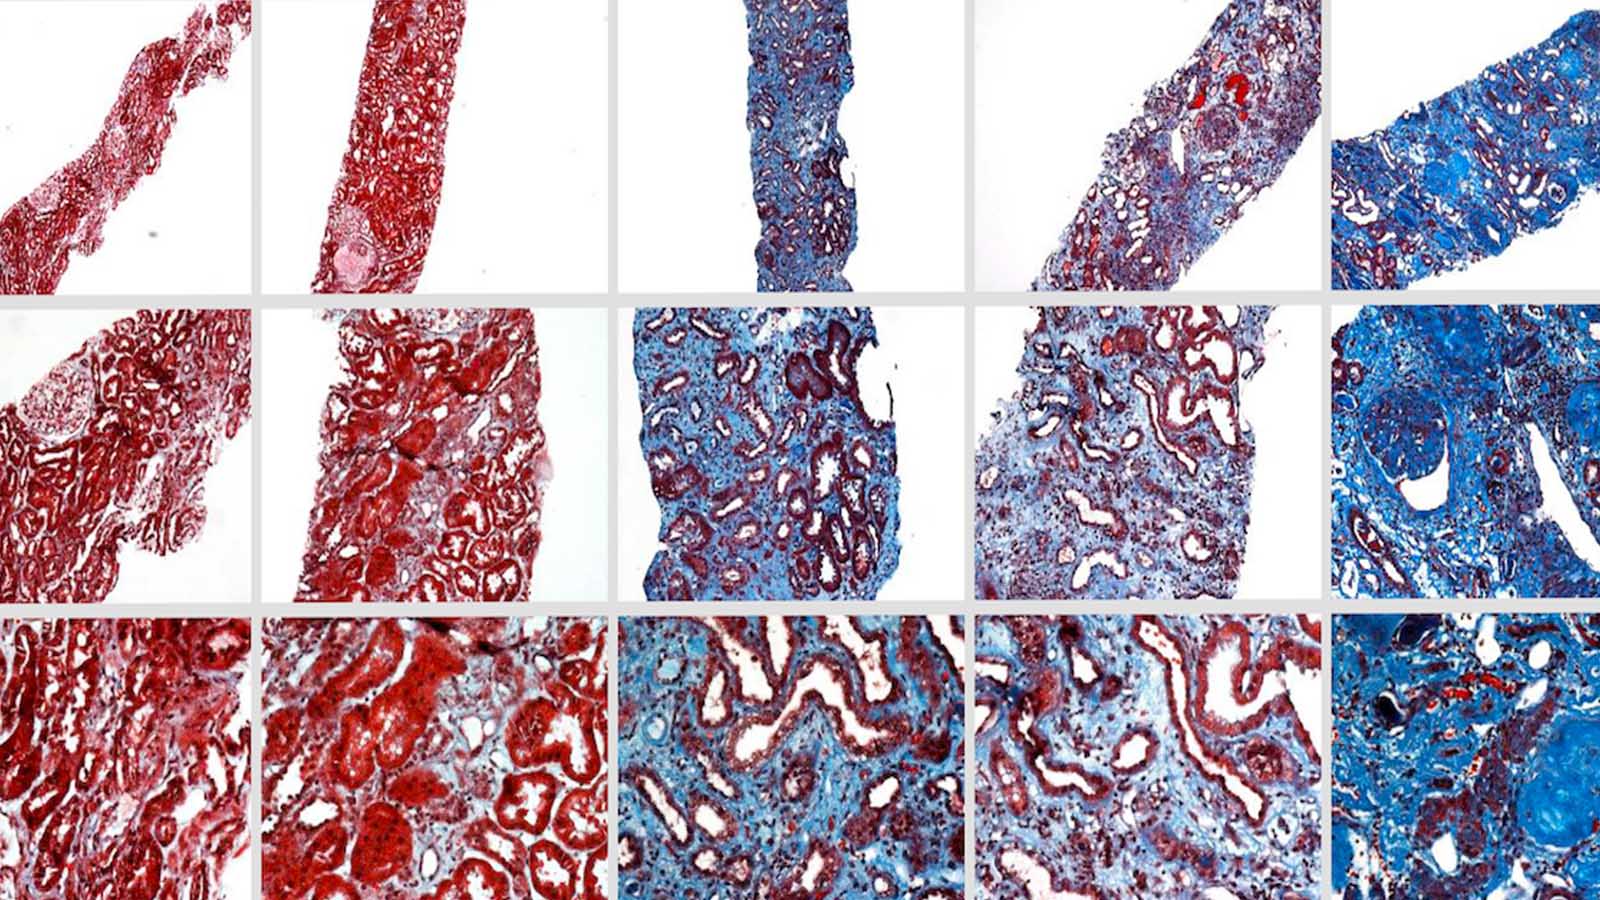

Activity in the Kolachalama Lab falls into two broad categories: machine learning and computer vision for precision medicine, and research into device-artery interactions, interfacial mechanics, and drug delivery. In his machine learning work, Kolachalama makes extensive use of BU’s Shared Computing Cluster housed at the MGHPCC.